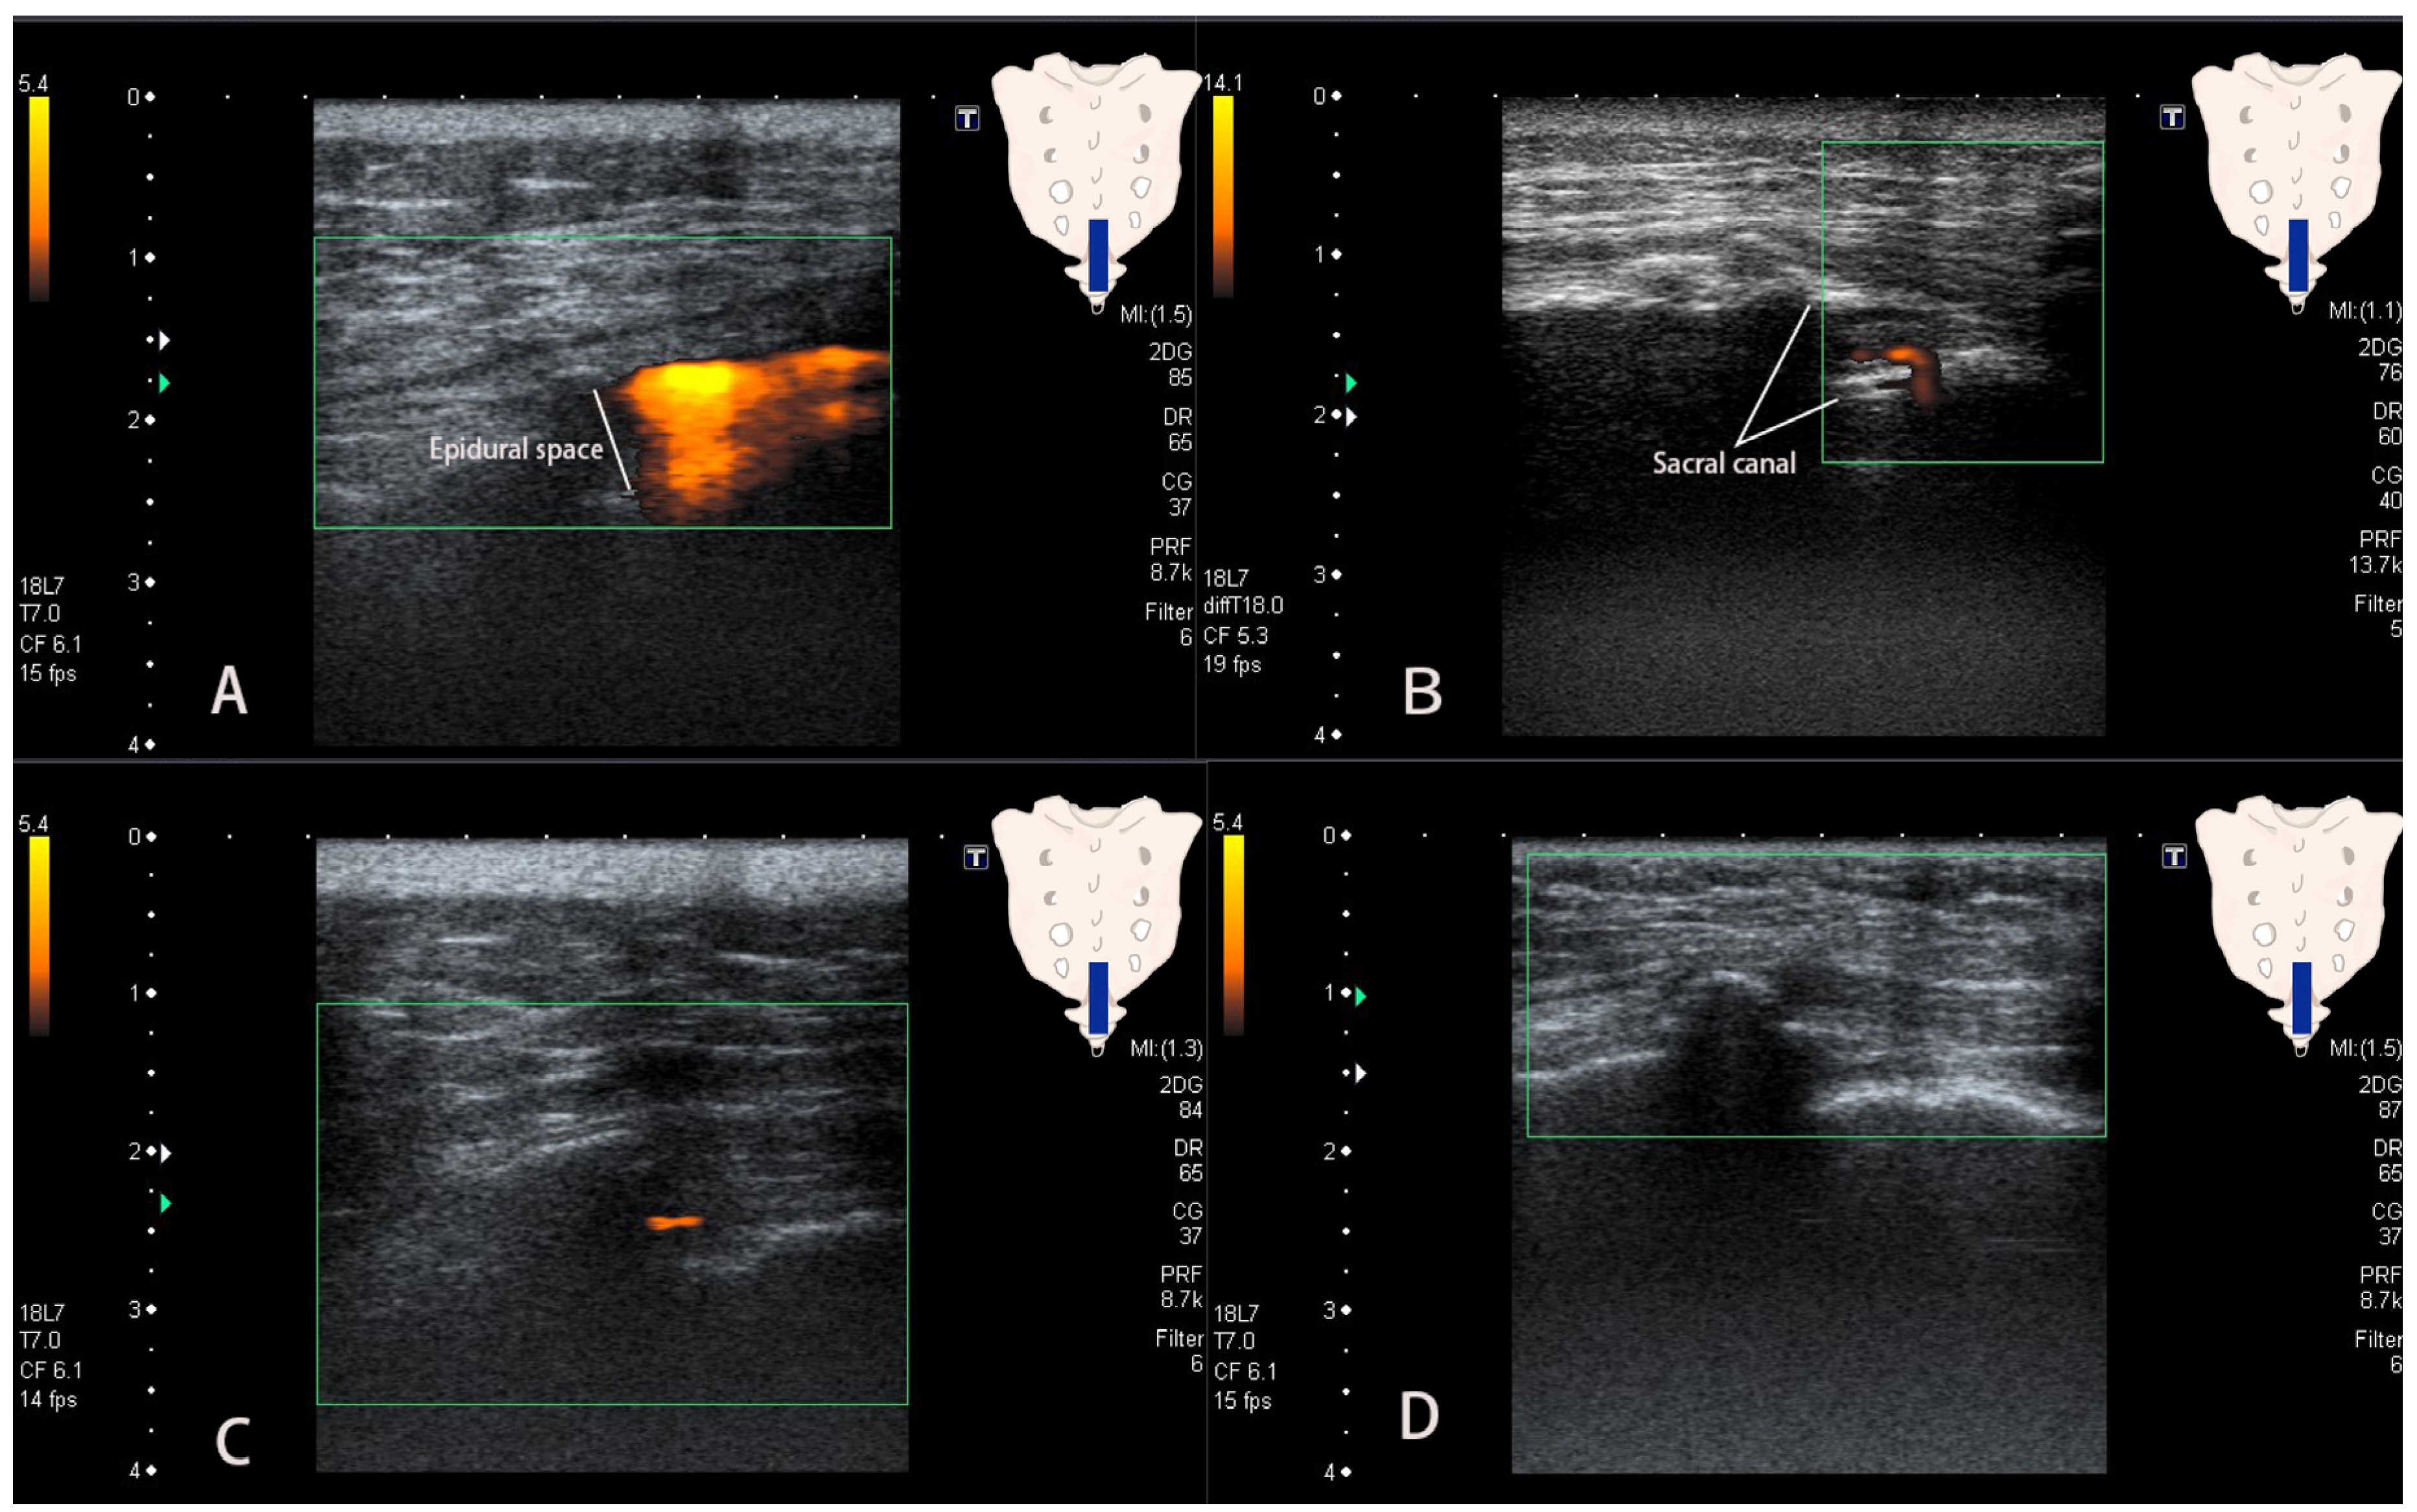

2.2. Procedures